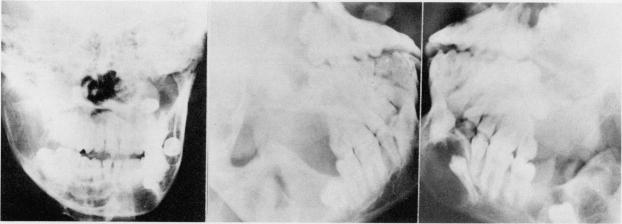

A Nigerian school boy with the syndrome of multiple jaw cysts, skeletal anomalies, and basal cell nevi is described and discussed. To the authors' knowledge, this is the first report of this syndrome in a black African.

本文描述并讨论了一名患有多颌囊肿、骨骼异常和基底细胞痣综合征的尼日利亚男学生。据作者所知,这是该综合征在非洲黑人中的首例报告。